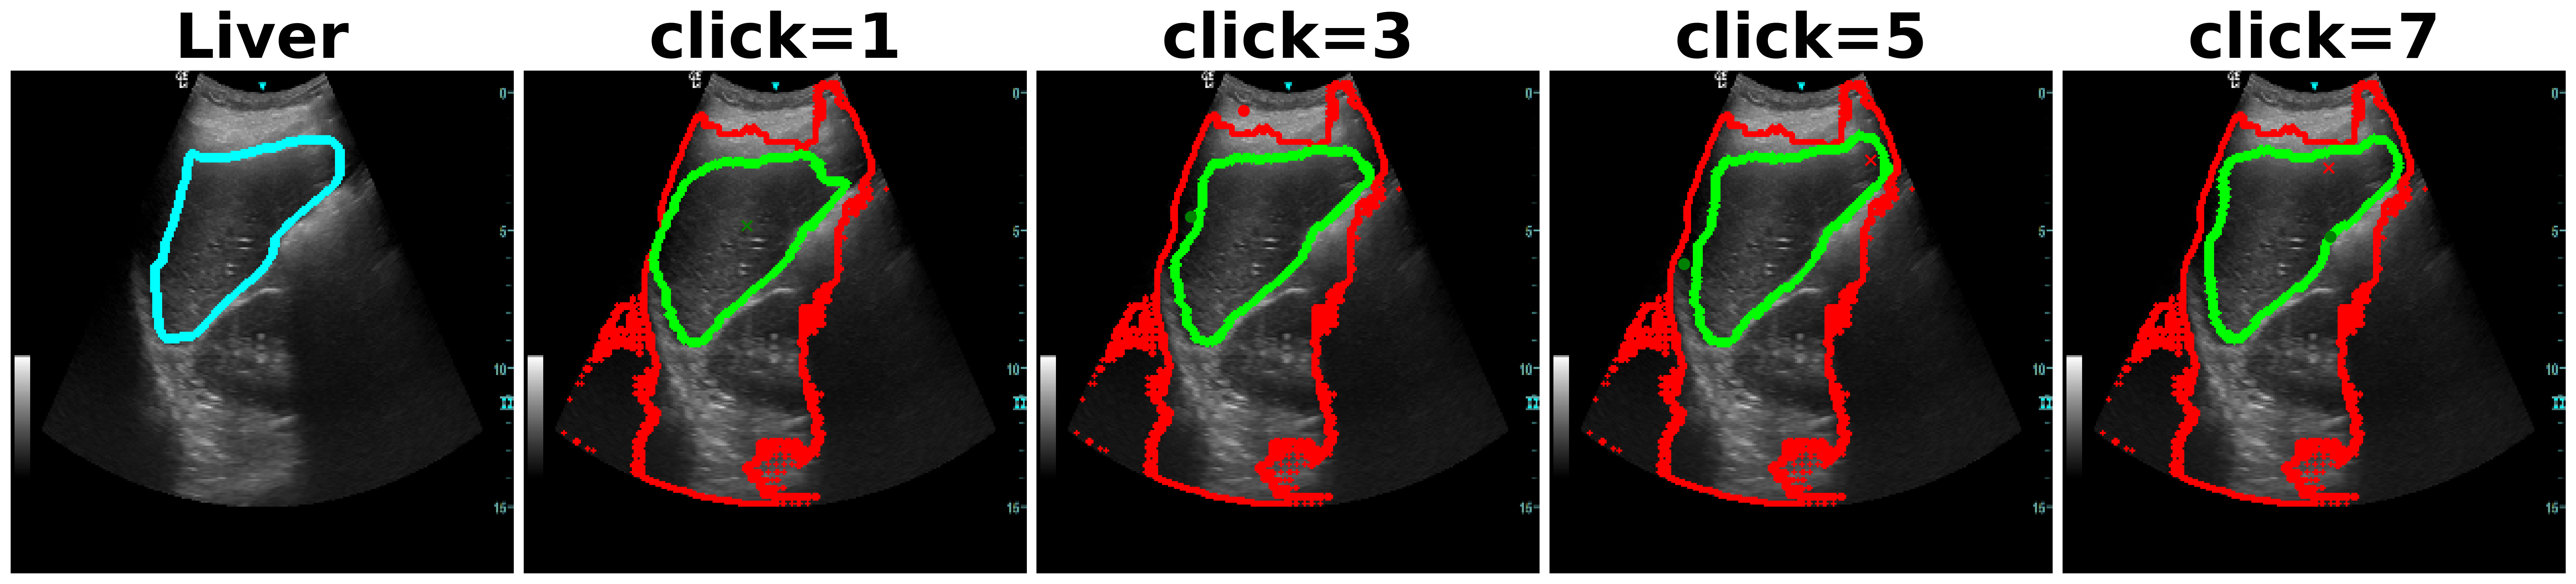

Utility of SAM[3] in medical imaging has been assessed recently in [27, 28, 29]. In an extensive experimental study [27], the authors find that while SAM obtains reasonable performance on different modalities, the performance is the poorest on ultrasound. This behavior is to be expected since ultrasound possesses unique characteristics like presence of scan cone, poor image quality and unique texture with speckles. Fig. 1a shows inefficiency of SAM and other methods on different anatomies, where after each click, our method outperforms consistently all the other methods.

SonoSAM achieves DSC on all data-sets and comfortably surpasses competing methods by a huge margin which struggle to cross even DSC. As shown in Table. 2, SAM model trained on natural images, under-performs significantly on ultrasound images often being poorer than SonoSAM in range of MaxDSC. Surprisingly, MedSAM which has been trained partly on ultrasound images is often the worst performer amongst all models, despite 3 of these datasets being ‘in-domain’ data-sets for MedSAM. Lack of training with clicks, severely hampers and infact deteriorates MedSAM’s performance. FocalClick model, performs reasonably on two data-sets - Liver and Fetal Head but takes several clicks to get to meaningful results, as shown Figure 7

One of the complaints with SAM model is that, the mask generated with user clicks (positive or negative clicks) are unintuitive and unpredictable. As shown in Figure 8, SAM often picks the entire FOV as the object and is unresponsive to multiple clicks. In contrast, SonoSAM’s responses are predictable, as demonstrated by smooth progression of predicted contours as shown in Figure 8